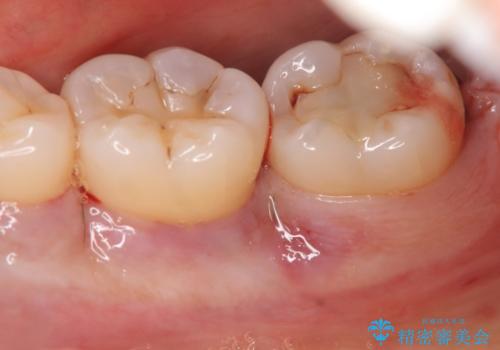

歯周病治療 → 歯槽骨の再生治療

歯がぐらぐら 再生療法で抜かずに残す 50代男性

歯周病を治す 再生療法 50代男性

骨を再生させて歯周病を治す 再生療法 50代男性